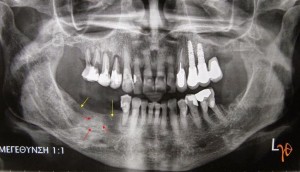

Στην ασθενή χορηγήθηκαν αντιβίωση και στοματοπλύσεις με χλωρεξιδίνη. Στην πανοραμική ακτινογραφία παρατηρήθηκε εκτεταμένη οστεολυσία στις θέσεις όπου αφαιρέθηκαν τα δύο οδοντικά εμφυτεύματα, αλλά και αυξημένη οστική πυκνότητα στον ενδιάμεσο χώρο(Εικόνα 2). Κλινικά δεν εμφανίστηκε απογυμνωμένο οστούν και η επούλωση των μαλακών μορίων της περιοχής ολοκληρώθηκε πλήρως μετά από ένα μήνα.